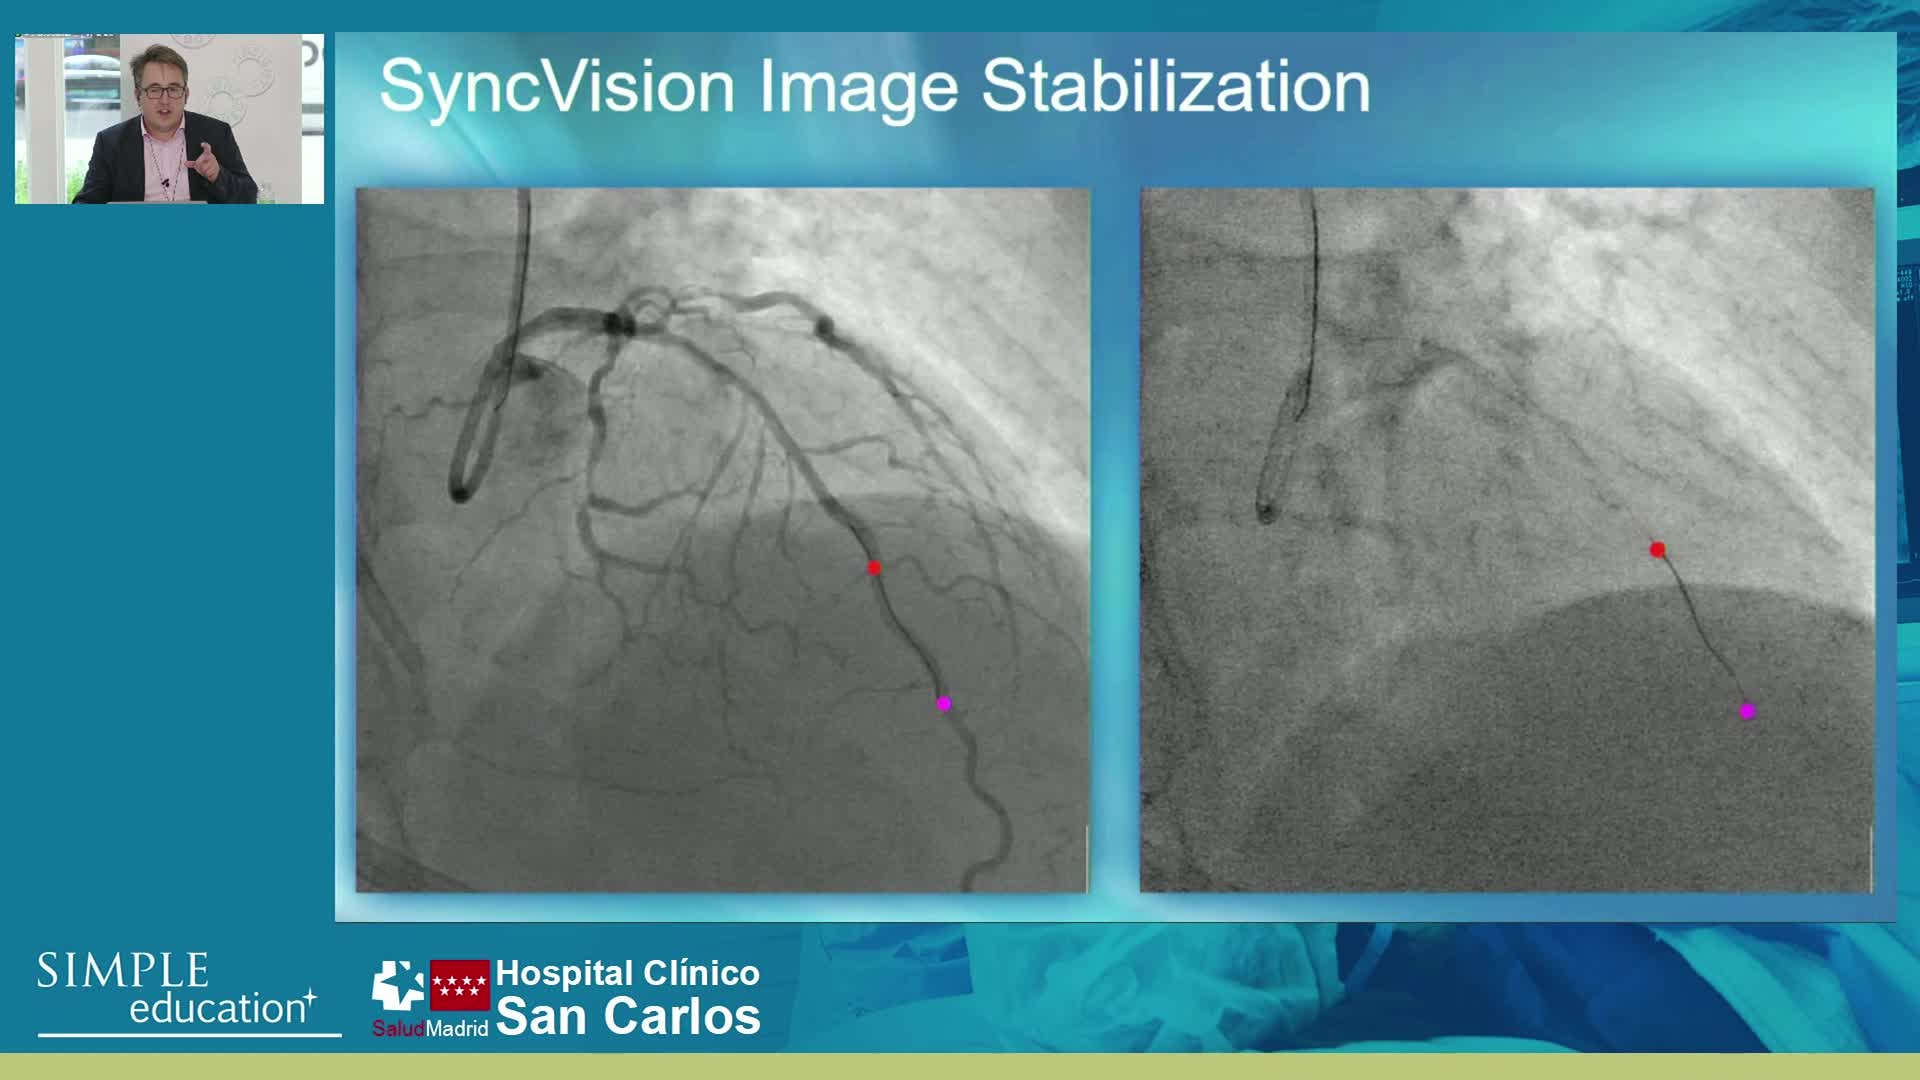

Understanding how SyncVision differs from other co-registration based technologies - Dr Justin Davies